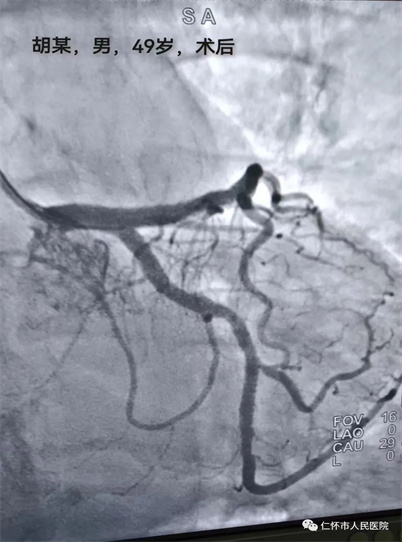

5月27日上午,急诊科接诊了一名58岁胡姓胸痛高危患者,当班医生徐力主治医师接诊后详询病史,患者自述突发胸痛、胸闷,逐转至抢救室,给予心电监护、吸氧,建立静脉通路,床旁查体,急查心电图及心梗三项检查,心电图结果提示急性下壁心肌梗塞,立即抢救,急请心血管内科医师会诊,当班医生一边说一边展开抢救。在予扩管、抗凝、抗血小板等药物治疗后,患者胸痛症状稍有缓解。经心血管内科医师苏如袖会诊后建议立即行急诊介入手术。就在这万分紧急时又再次接诊一位49岁胡姓胸痛患者,急诊科医师徐力立即上报余兴素总住院医师参与抢救,经询问病史、查体及相关辅查后患者同样诊断为急性下壁心肌梗死,但目前只有一个空台可以手术,这似乎多了那么一丝微妙在其中,为了两名患者得到有效的快速救治,我院急诊科副主任医师罗杨松及苏如袖医师当机立断,根据两名患者心电图情况一名患者立即行经皮冠状动脉介入治疗(PCI),另一名患者急诊溶栓后再行介入。

在我院急诊科、心血管内科和介入科的齐心协力下,两名患者现均脱离了生命危险,并得到有效救治。